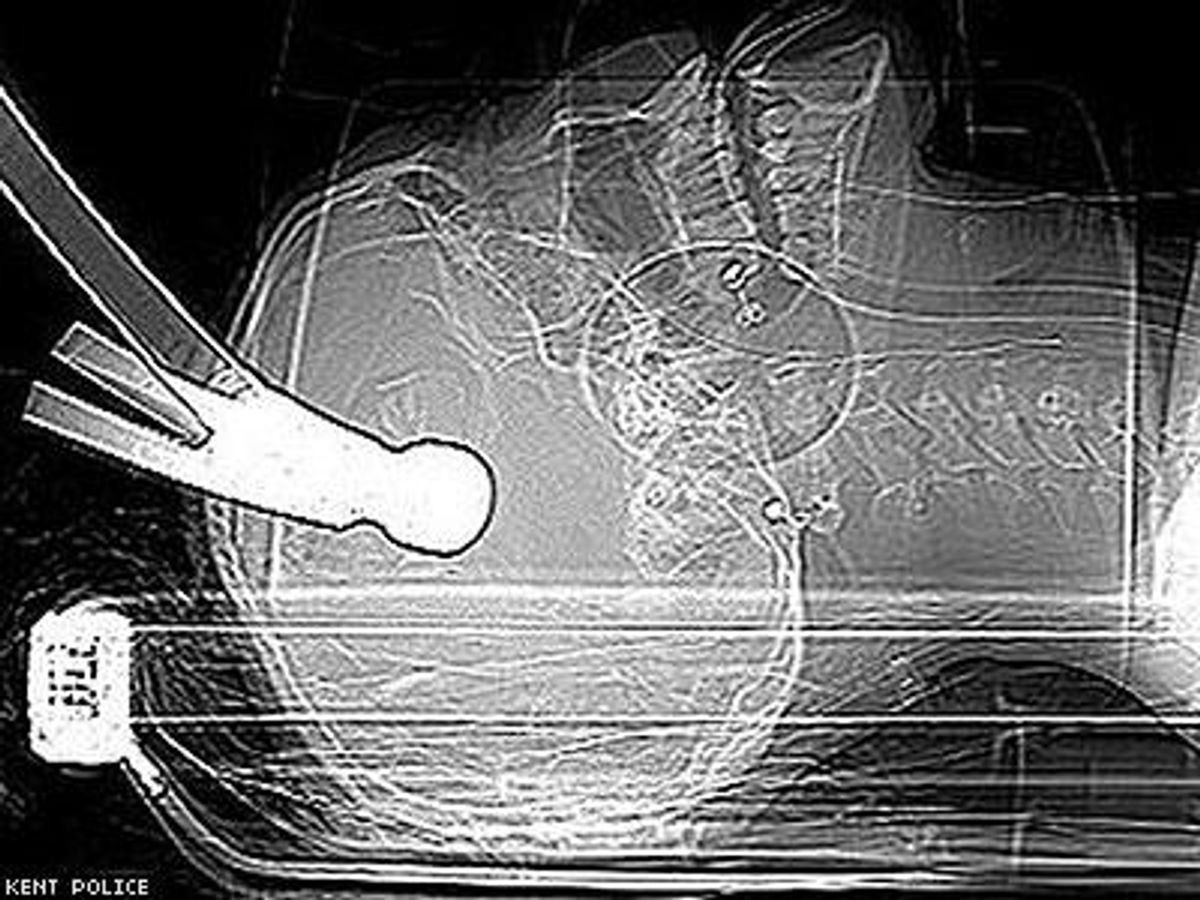

Prosecutors told the court that Kent Police found that Huntley was still alive, lying on an inflated airbed with a hammer embedded in his skull. Huntley and Williams had been matched as flatmates by their landlord. The night of the attempted murder was Huntley's first night in his new home.

"To hit someone more than once with a hammer in their sleep hard enough for the hammer to be embedded in their head clearly demonstrates an intention to kill them," prosecutor Philip Bennet told the court, according to the Standard.

Huntley suffered a depressed skull fracture and a penetrating brain injury, but miraculously survived the near-fatal injury, reports the Standard. His family has asked for privacy as Huntley recovers from brain damage caused by the attack.